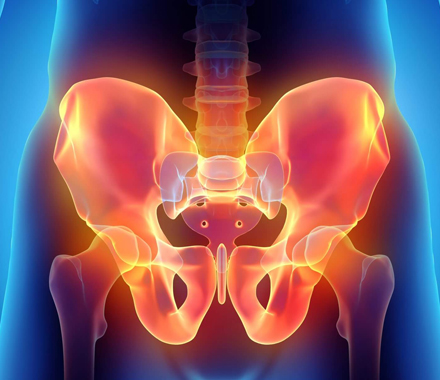

Pelvic Pain

Pelvic pain is a common issue experienced by many women, and can be caused.....

Pelvic Pain